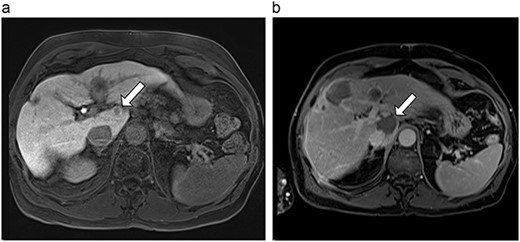

(a) Pre-ablation MRI demonstrating 15 mm lesion in caudate lobe of liver (image degraded by motion artifact). (b) Post-ablation MRI (20 days postoperatively) demonstrating 35 mm complete ablation of caudate lesion (image degraded by motion artifact).

| 2 (4a,b) | 67, M | Colon adenocarcinoma | 8 cycles capecitabine and oxaliplatin | 6 | Laparoscopic microwave ablation | 15 | 35 | 20 | 6 | No |